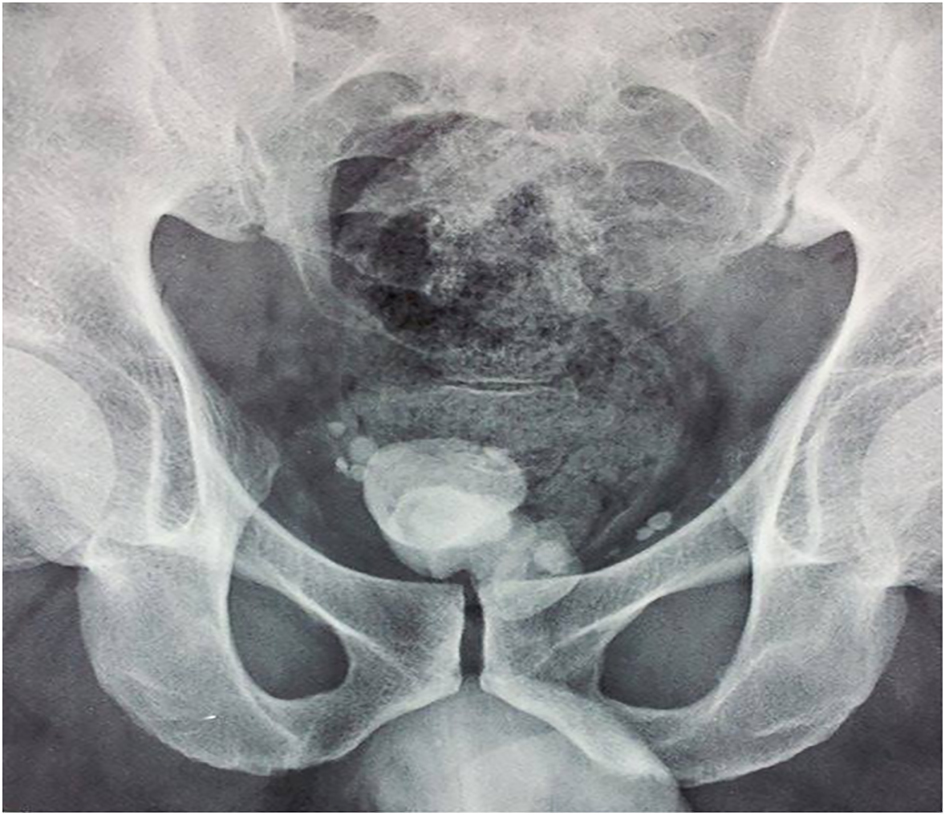

A kidney, ureter, and bladder (KUB) X-ray and abdominal ultrasound were performed and objectived bladder calculus of 6 cm without upper urinary tract calculi (Fig. 1), significant post void urine volume and thinking of the bladder wall. Laboratory studies showed urine culture grew Klebsiella pneumoniae. After antibiotic therapy, the patient underwent suprapubic cystotomy; calculi were located in the prostatic urethra and removed through bladder neck incision. At 3-month follow-up, the patient was free of symptoms. However, retrograde ejaculation was reported. Retrograde cystography objectived stone free large prostatic fossa and no urethral stenosis.

![]() Click for large image | Figure 1. KUB X-ray showing the first prostatic urethral calculus. |